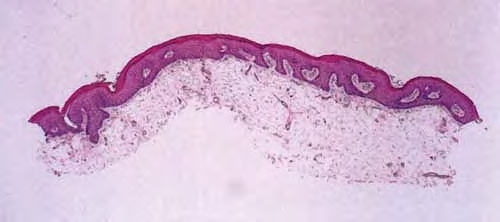

Focal dermal hypoplasia (Goltz-Godin syndrome) = نقص تصنع الادمة البؤري = متلازمة غولتز كودن